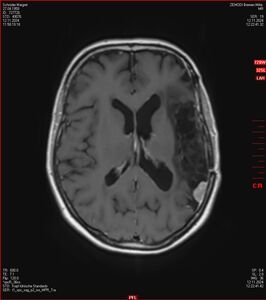

MRT vom 12. November 2024

So nun ein paar neue Bilder aus meinem Kopf. (Durch klicken bekommt man eine größe Ansicht eines Einzelbildes).

Die letzten drei Bilder Zeigen aus meiner Sicht den Tumor, der im Jahr 2021 bestrahlt wurde.